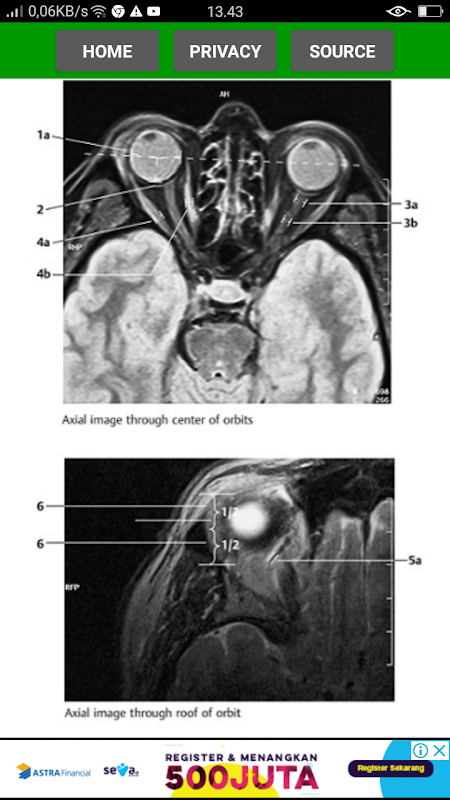

The key for any beginning radiologist who wishes to recognize pathological findings is to first acquire an ability to distinguish them from normal ones. This outstanding guide gives beginning radiologists the tools they need to systematically approach and recognize normal MR and CT images.

* Reference-quality images from the author's own teaching files show all standard normal findings as seen in CT and MRI